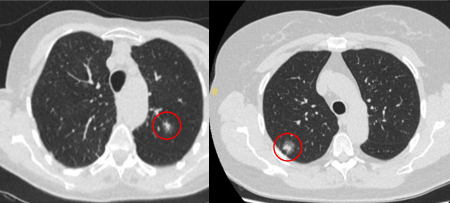

The appearance of the adjacent fissure, as well as any visible pleural ‘tags’, are signs that need to be considered when evaluating perifissural or peripheral solitary lung nodules. A retracted fissure associated with a non-smooth nodule increases the possibility of malignancy.[33][34][Figure caption and citation for the preceding image starts]: Computed tomography (CT) sections from two cases with benign perifissural nodules. Note the smooth margins and the normal undisturbed adjacent fissureFrom the collection of Dr George Tsaknis, MD, PhD, FRCP(London), MRQA, MAcadMEd, PGCert; used with permission [Citation ends].

[Figure caption and citation for the preceding image starts]: Computed tomography (CT) showing examples of malignant perifissural nodules. Note the spiculated edge of the nodules and the evident retraction of the adjacent fissure. Both resection tissue analyses confirmed adenocarcinoma of lungFrom the collection of Dr George Tsaknis, MD, PhD, FRCP(London), MRQA, MAcadMEd, PGCert; used with permission [Citation ends].